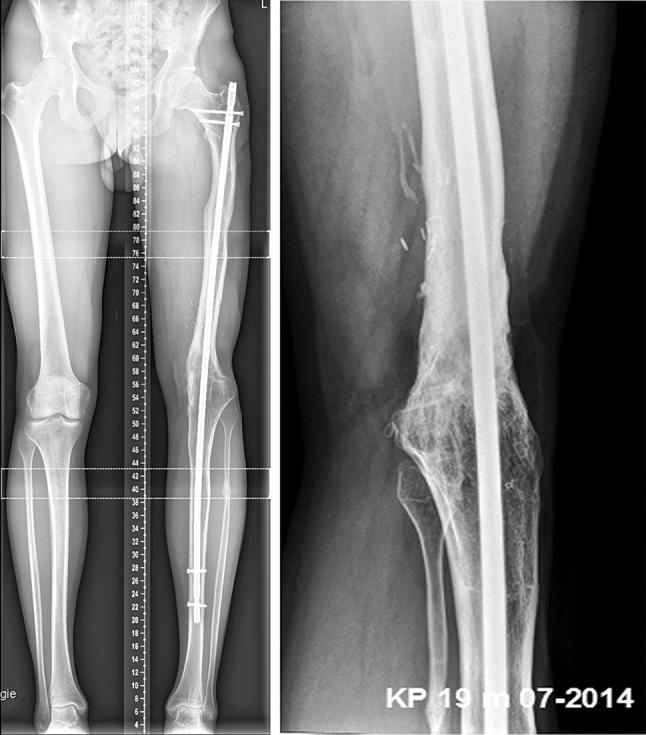

采用延长后髓内钉技术对股骨远端部分截肢伴广泛节段性骨缺损进行保肢治疗:1例病例报告

Limb salvage in a partially amputated distal femur with extensive segmental bone loss using the nailing after lengthening technique: a case report.

Segmental long bone defects resulting from high-energy trauma with severe soft tissue loss are difficult problems to manage. Amputation was for a long time the primary mainstay of treatment. This is the report on a 15-year-old male patient who sustained a third-degree open, traumatic fracture with partial amputation of the left distal femur and extensive bone loss of 26 cm. Successful limb salvage was performed after vascular repair, shortening of the bone defect, primary placement of an antibiotic cement spacer and simple external fixation. This was followed by bifocal lengthening modifying the simple frame until limb equality was achieved and secondary intramedullary nailing 11 months after injury.

摘要

因高能创伤导致的节段性长骨缺损伴有严重软组织缺失,是治疗上的难题。长期以来,截肢一直是主要的治疗手段。本文报告了一名15岁男性患者,其遭受了左股骨远端三度开放性创伤骨折,伴有部分截肢及26厘米的广泛骨质缺损。在进行血管修复、缩短骨缺损、一期植入抗生素骨水泥间隔物及简单外固定后,成功实施了保肢手术。随后进行双焦点延长,对简单外固定架进行改良,直至双下肢等长,伤后11个月进行二期髓内钉固定。